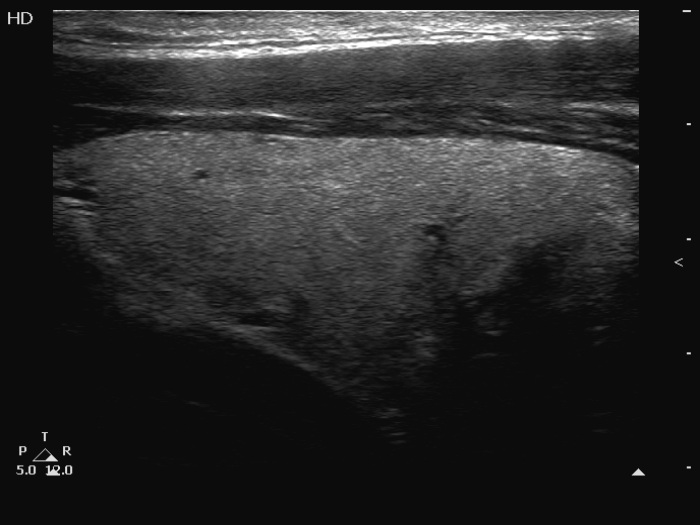

Clinical presentation: A 33-year-old man requested evaluation of a nodule which was discovered by himself 6 months ago.

Palpation: a firm nodule in the left lobe.

Ultrasonography. The thyroid was echonormal. There was a moderately hypoechoic nodule in the ventromedial part of the left lobe. The nodule had equivocal intranodular echogenic figures and showed blurred borders. The intranodular vascularization was increased.

Cytology resulted in papillary cancer.

Histopathology revealed a papillary cancer.